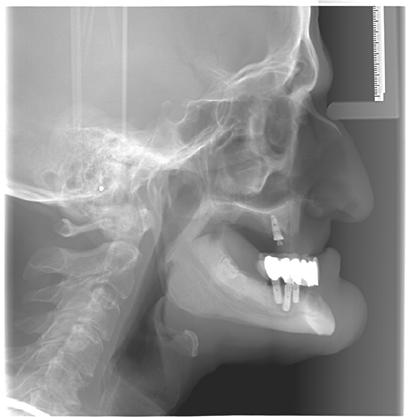

20–22. ábra: 2017-es, 2019-es és 2022-es panorámaröntgen-felvételek.

lási csavarokat (PEEK titáncsavarral) maximum 15 Ncm-rel húztuk meg (3–6. ábra). Az összes implantátum kiváló stabilitást mutatott (a mérésekhez Periotestet használtunk, a Medizintechnik Gulden jóvoltából), és teljesen osszeointegrálódott. Ezt a radiológiai vizsgálatok is megerősítették.

tottuk (az okklúziós koncepciók alapján az implantációs pótlások nem voltak vezető fogak, és csak könnyű érintkezéseket alakítottunk ki, amelyeket artikulációs papírral ellenőriztünk). A páciensek instrukciókat kaptak a megfelelő szájhigiénére vonatkozóan, összpontosítva a fogköz kefékkel történő tisztítására. Végső kontroll röntgenfelvétel készült. A PEEK felépítmény nem radioopák, így az implantátum és a korona közötti távolság könnyen meghatározható a röntgenfelvételen: a felépítmény megfelelően illeszkedik az implantátumban, ha az implantátum válla és a korona alsó széle közötti rés 0,55 mm a röntgenfelvételen (8–11. ábra)